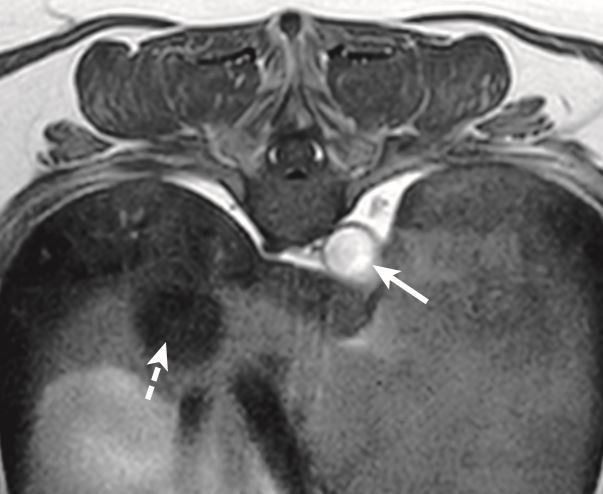

What artifact is this?

A

CSF flow artifact causing a pseudolesion

What is this artifact?

Pulsatility artifact/ghosting